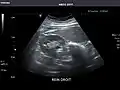

Right kidney -